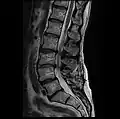

MRI lumbar spine with degeneration, post-hemilaminectomy L4-5 (sagittal T2 FRFSE) -

MRI lumbar spine with degeneration, post-hemilaminectomy L4-5 (sagittal T1 FSE) -

MRI lumbar spine with degeneration, post-hemilaminectomy L4-5 (sagittal FAST STIR) -